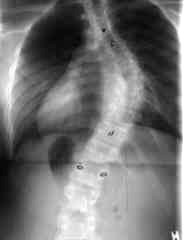

das ist eine verkrümmung der wirbelsäule. kann man sich am besten s-förmig vorstellen. es gibt verschiedene fomen der wirbelsäule: nach rechts, nach links, 2-bögig, 3-bögig, 4-bögig, nach hinten nach vorne etc.

ich hab häufigste form. nämlich 3-bögig nach rechts (siehe bild).

0° wäre ideal - keine skoliose; gibts aber selten. ab 10° spricht man von skoliose. ich hab mit meinen 50° im hauptbogen schon ne mittelschwere skoliose. wobei es mit über 100° aber weitaus heftiger geht.

diagnose: ideopathische skoliose; 50° oben, 37° unten; krankengymnastik; korsettbehandlung; stationärer aufenthalt.